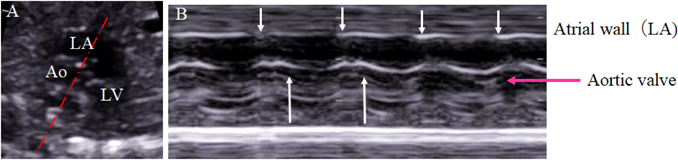

3) Evaluation of Ventricular Systolic Function

1. Fractional Shortening of the Ventricular Inner Diameter

Ventricular contractility is evaluated using the shortening rate of each ventricle. The cursor of the ultrasonography device is placed perpendicular to the septum beneath the AV valve in the 4CV. The movements of the mitral and the tricuspid valves are recorded simultaneously on M mode. This is helpful to identify systolic and diastolic phases. Fractional shortening (FS) is calculated with the difference between the end-diastolic and the end-systolic diameters of the ventricular cavity divided by the end-diastolic diameter.

FS=(end-diastolic inner diameter−end-systolic inner diameter)/end-diastolic inner diameter

The normal FS range (0.28–0.40) is independent of gestational age.90) If the position of a fetus renders the assessment of the ventricular size difficult, the modified Simpson method can be applied for determining the contraction rate tracing the ventricular cavity.91) Measurement errors, which could be rather large in fetal geometry, need attention when calculating FS whichever the methods are chosen.